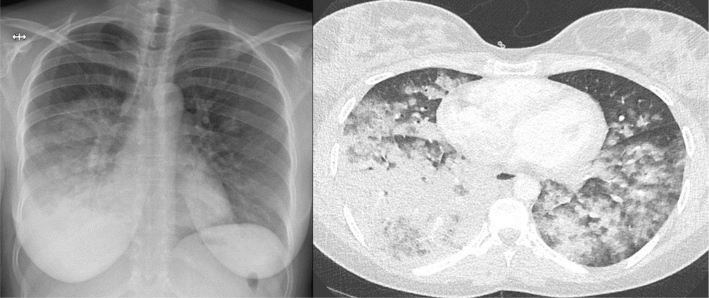

Case description: This case report describes a 20-year-old African woman with a history of ulcerative colitis who developed diffuse alveolar haemorrhage in the setting of elevated proteinase 3 (PR3)-ANCA. She was treated for ANCA-associated vasculitis with corticosteroids, plasma exchange, and rituximab, leading to a complete resolution.

Abstract Image